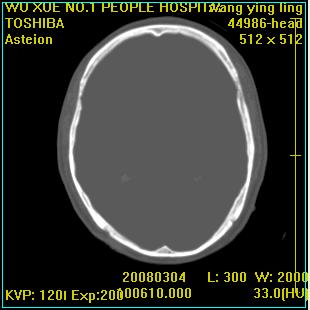

标题: CT12023:女,50岁,头部包块二月,伴轻微头痛,不伴发热。 [打印本页]

标题: CT12023:女,50岁,头部包块二月,伴轻微头痛,不伴发热。

这种病例还是比较多见,起源于颅骨板障,向颅内和颅外生长,考虑血管瘤或嗜酸性肉芽肿,要是有增强ct就好了。

多发溶骨性破坏,骨嗜酸性肉芽肿可能,转移瘤待排除,建议进一步检查。

破坏区边界较清楚,还是考虑良性病变---嗜酸性肉芽肿可能。

病灶呈溶骨性骨破坏,考虑嗜酸性肉芽肿可能转移瘤不除外建议追查病史并进一步检查